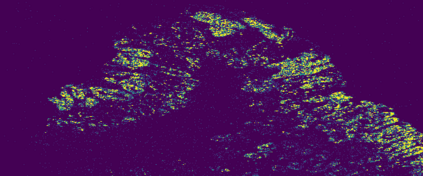

The usage of chemical imaging technologies is becoming a routine accompaniment to traditional methods in pathology. Significant technological advances have developed these next generation techniques to provide rich, spatially resolved, multidimensional chemical images. The rise of digital pathology has significantly enhanced the synergy of these imaging modalities with optical microscopy and immunohistochemistry, enhancing our understanding of the biological mechanisms and progression of diseases. Techniques such as imaging mass cytometry provide labelled multidimensional (multiplex) images of specific components used in conjunction with digital pathology techniques. These powerful techniques generate a wealth of high dimensional data that create significant challenges in data analysis. Unsupervised methods such as clustering are an attractive way to analyse these data, however, they require the selection of parameters such as the number of clusters. Here we propose a methodology to estimate the number of clusters in an automatic data-driven manner using a deep sparse autoencoder to embed the data into a lower dimensional space. We compute the density of regions in the embedded space, the majority of which are empty, enabling the high density regions to be detected as outliers and provide an estimate for the number of clusters. This framework provides a fully unsupervised and data-driven method to analyse multidimensional data. In this work we demonstrate our method using 45 multiplex imaging mass cytometry datasets. Moreover, our model is trained using only one of the datasets and the learned embedding is applied to the remaining 44 images providing an efficient process for data analysis. Finally, we demonstrate the high computational efficiency of our method which is two orders of magnitude faster than estimating via computing the sum squared distances as a function of cluster number.